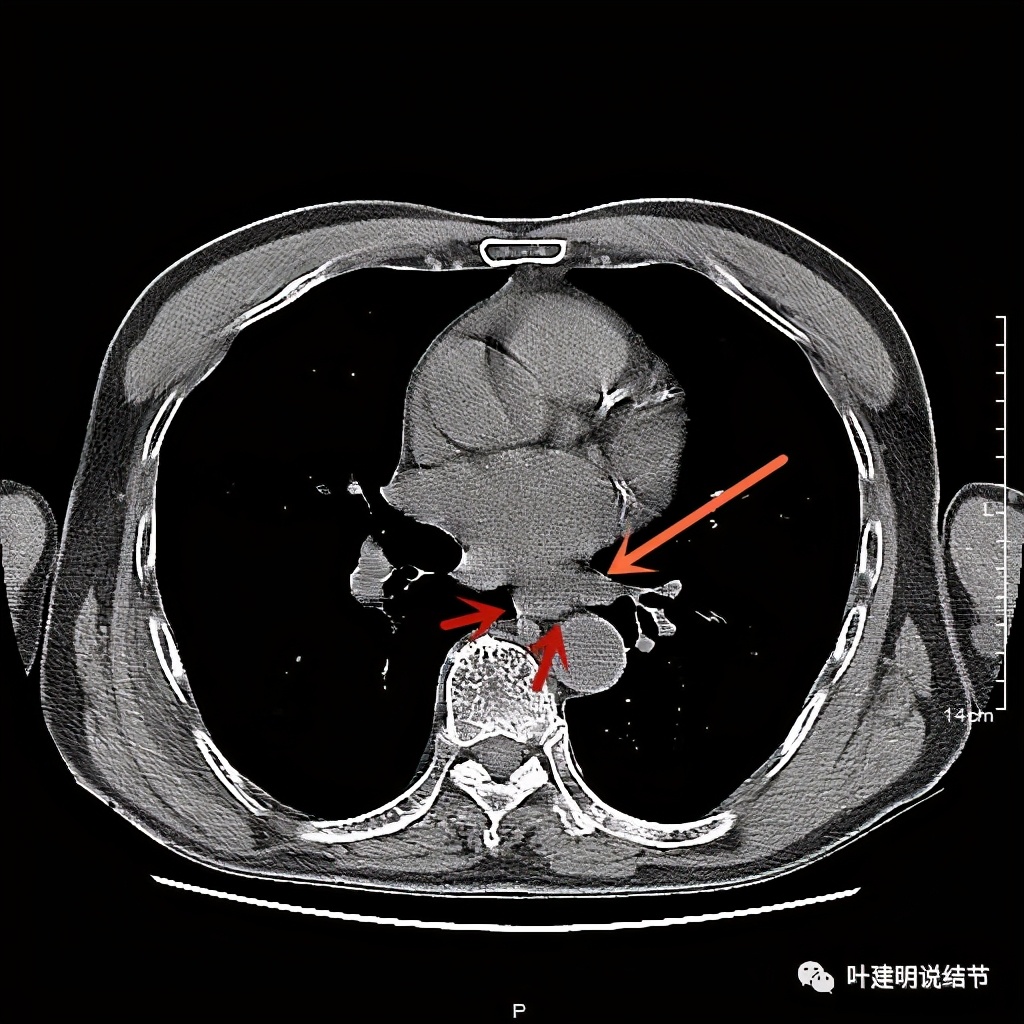

活检后食管是鳞癌,结肠是腺癌。下面是其术前CT的图像:

红色示肿瘤

红色示肿瘤,桔色示下肺静脉,与主动脉间间隙清楚